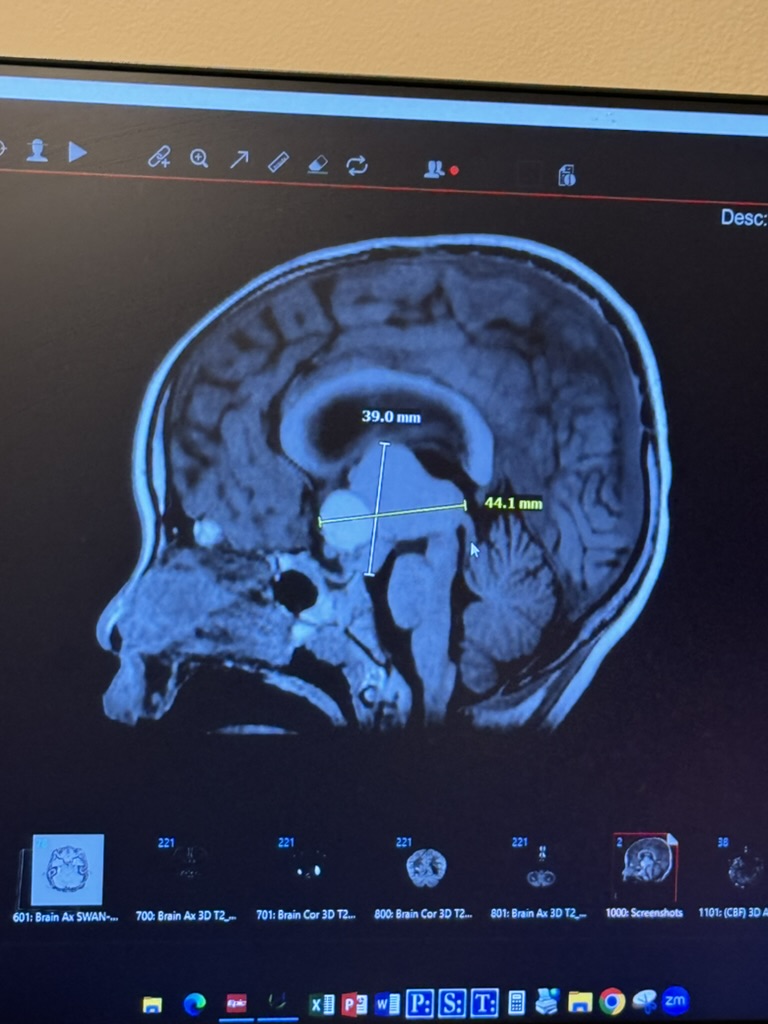

Mira Chen a Runway pénzügyi startup igazgatójának és társalapítójának, Siqi Chennek a legfiatalabb gyermeke. Miránál tavaly diagnosztizálták az Adamantinomatous Craniopharyngioma-t, egy rendkívül ritka agydaganatot. Bár a daganat önmagában “jóindulatú”, elhelyezkedése miatt idővel súlyos problémákat okozhat az ebben érintett betegeknek.